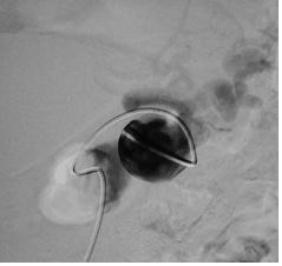

栓塞开始:先致密填塞静脉池,再致密栓塞滋养动脉 |

造影显示部分静脉池不显影,滋养动脉闭塞 |

选择性肺动脉造影显示另一支滋养动脉和静脉池。 |

选择性进入滋养动脉 |